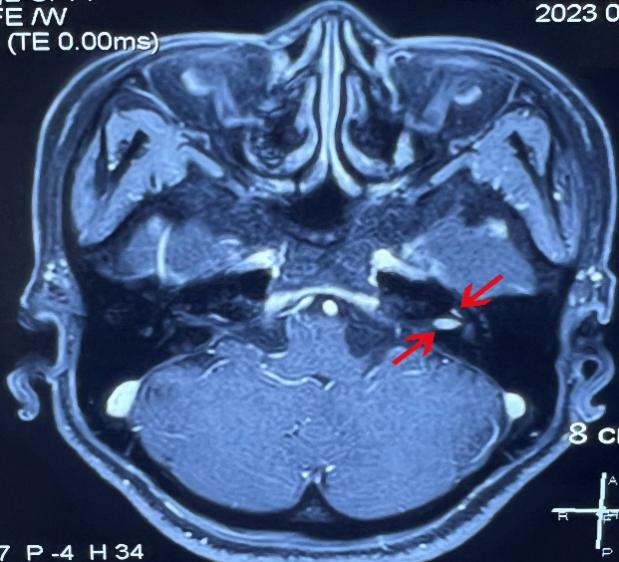

患者女,48岁,以“左耳听力下降伴间歇性眩晕1年”之主诉入院。纯音听阈示:左耳全聋;MRI发现左侧耳蜗-内听道占位,遂以听神经瘤收入我科。术前仔细阅片并与家属充分沟通,团队制定了详细手术方案,考虑到肿瘤侵及耳蜗底钻,且内听道部分6mm×3mm大小, 决定采用耳内镜下经过耳道、鼓岬入路切除肿瘤。但该患者颈静脉球高位,手术操作空间小、难度大,将耳后切开、显微镜下经迷路切除肿瘤做为备选方案。